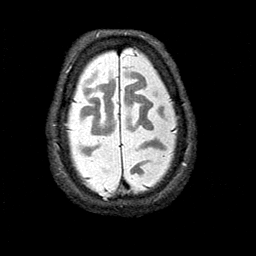

Alzheimer's disease MR T2-weighted -- Slice #41

[Home][Help][Clinical][Tour 1][Tour 2] Slice 41